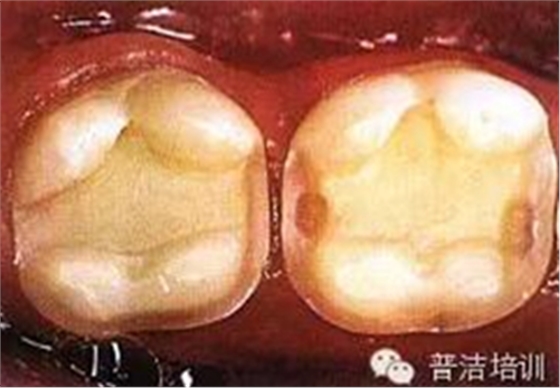

三、牙體預(yù)備完成,,邊緣預(yù)備短斜面(45度),短斜面這點很多書上沒具體說,想想還是有必要的,但在金屬嵌體和瓷嵌體就沒必要了。其實預(yù)備這一步驟沒什么高深莫測的,多加訓(xùn)練,端正態(tài)度就可以。

四、如果在預(yù)備過程中,有比較明顯的倒凹存在時,可以在軸壁以及軸髓線角處涂一層蠟,并可作為樹脂水門汀預(yù)留在空間,但不可涂抹過多。